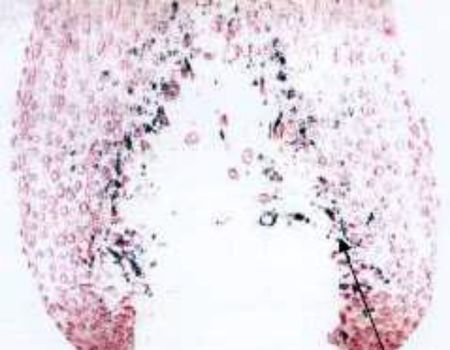

Melanocyte produces melanin pigment.

Melanocyte does not produce melanin pigment.

Melanocyte is completely lost from hair bulb part.